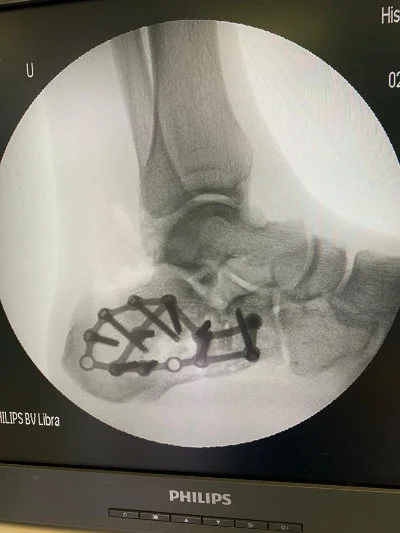

Görüntüleri büyütmek için resmin üstüne tıklayınız.